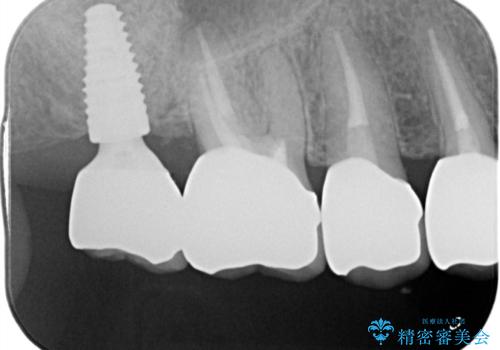

自然な仕上がりとインプラントによる咬合機能の回復に満足いただくことができました。

装着されているクラウンを除去し、自然な色調のジルコニアクラウンによる審美生の改善、インプラントを用いた欠損部の機能回復を計画します。

- 88万円(インプラント・チタンカスタムアバットメント・ジルコニアクラウン×4・仮歯×4)費用は治療当時の料金となります